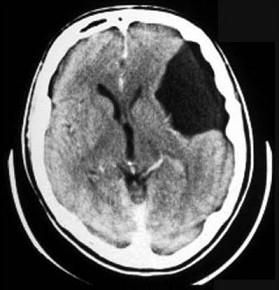

问题 根据图示,应诊断为何种神经系统先天性疾病 ( )

选项 A、先天性脑积水 B、蛛网膜囊肿 C、Litter病 D、无脑畸形 E、颅底凹陷症 一、单项选择题

答案 B